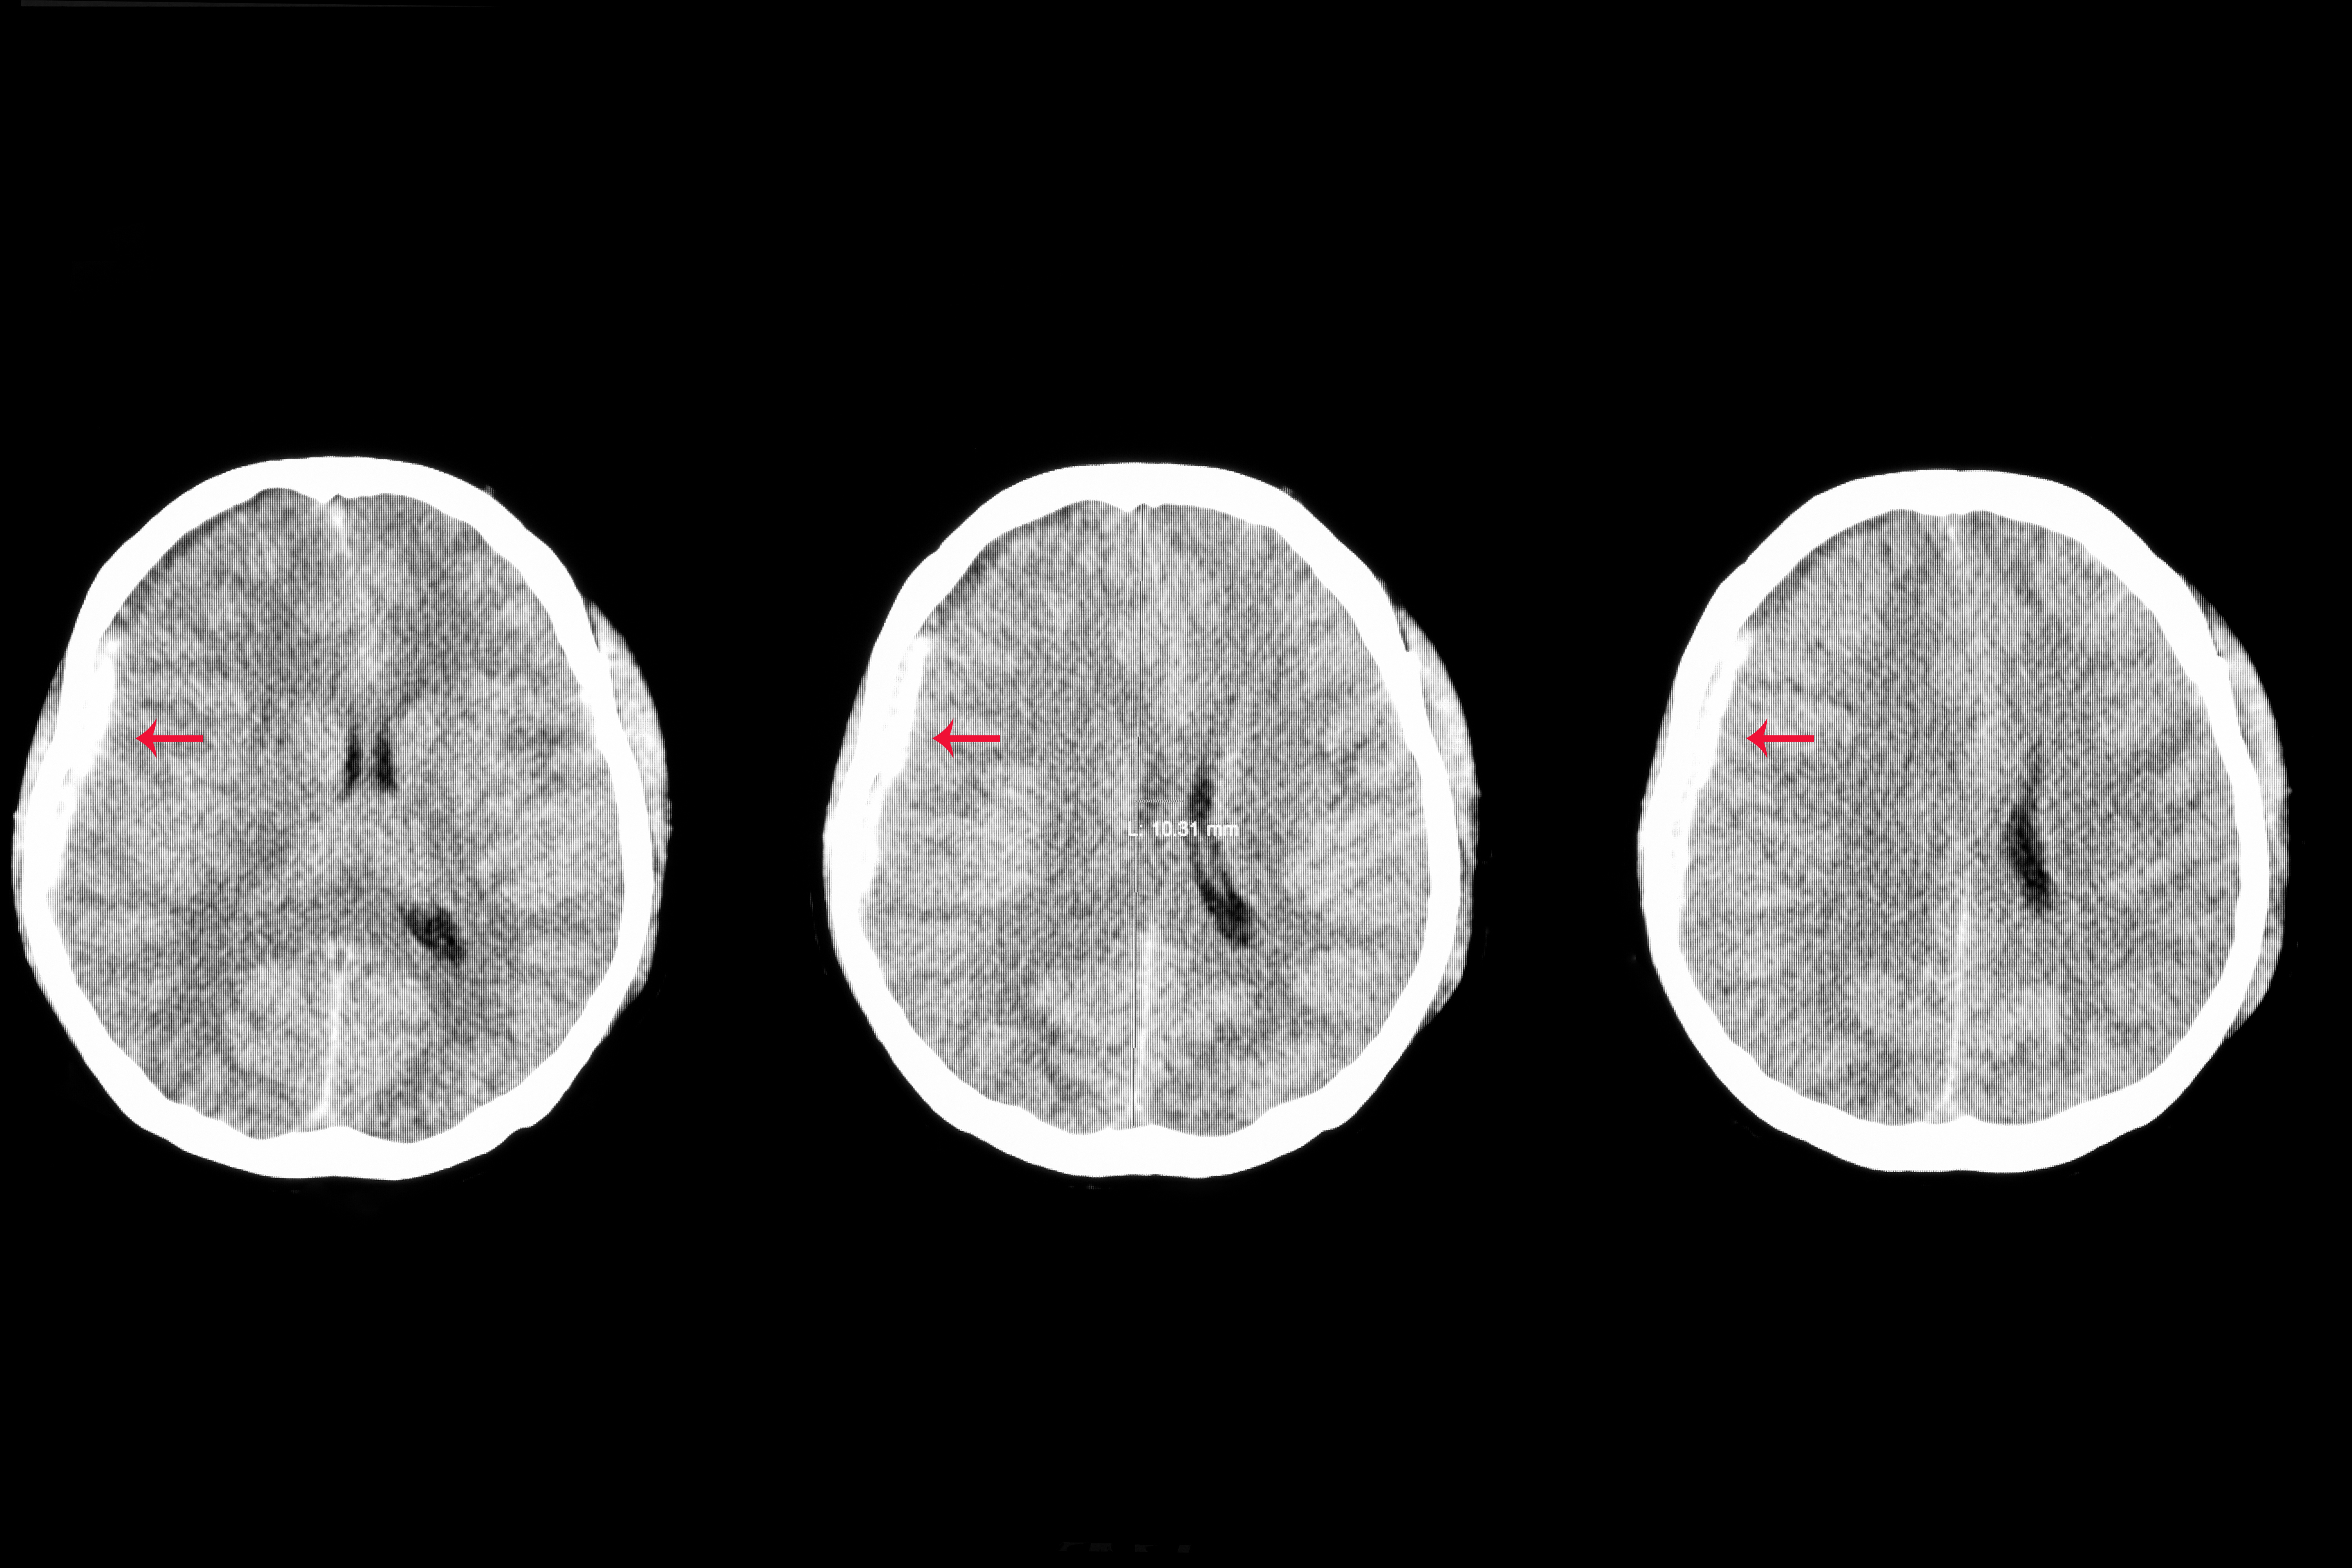

A 3D whole brain convolutional neural network could provide enhanced sensitivity and specificity for diagnosing intracranial hemorrhages on computed tomography, according to new research presented at the Society for Imaging Informatics in Medicine (SIIM) conference in Kissimmee, Fla.